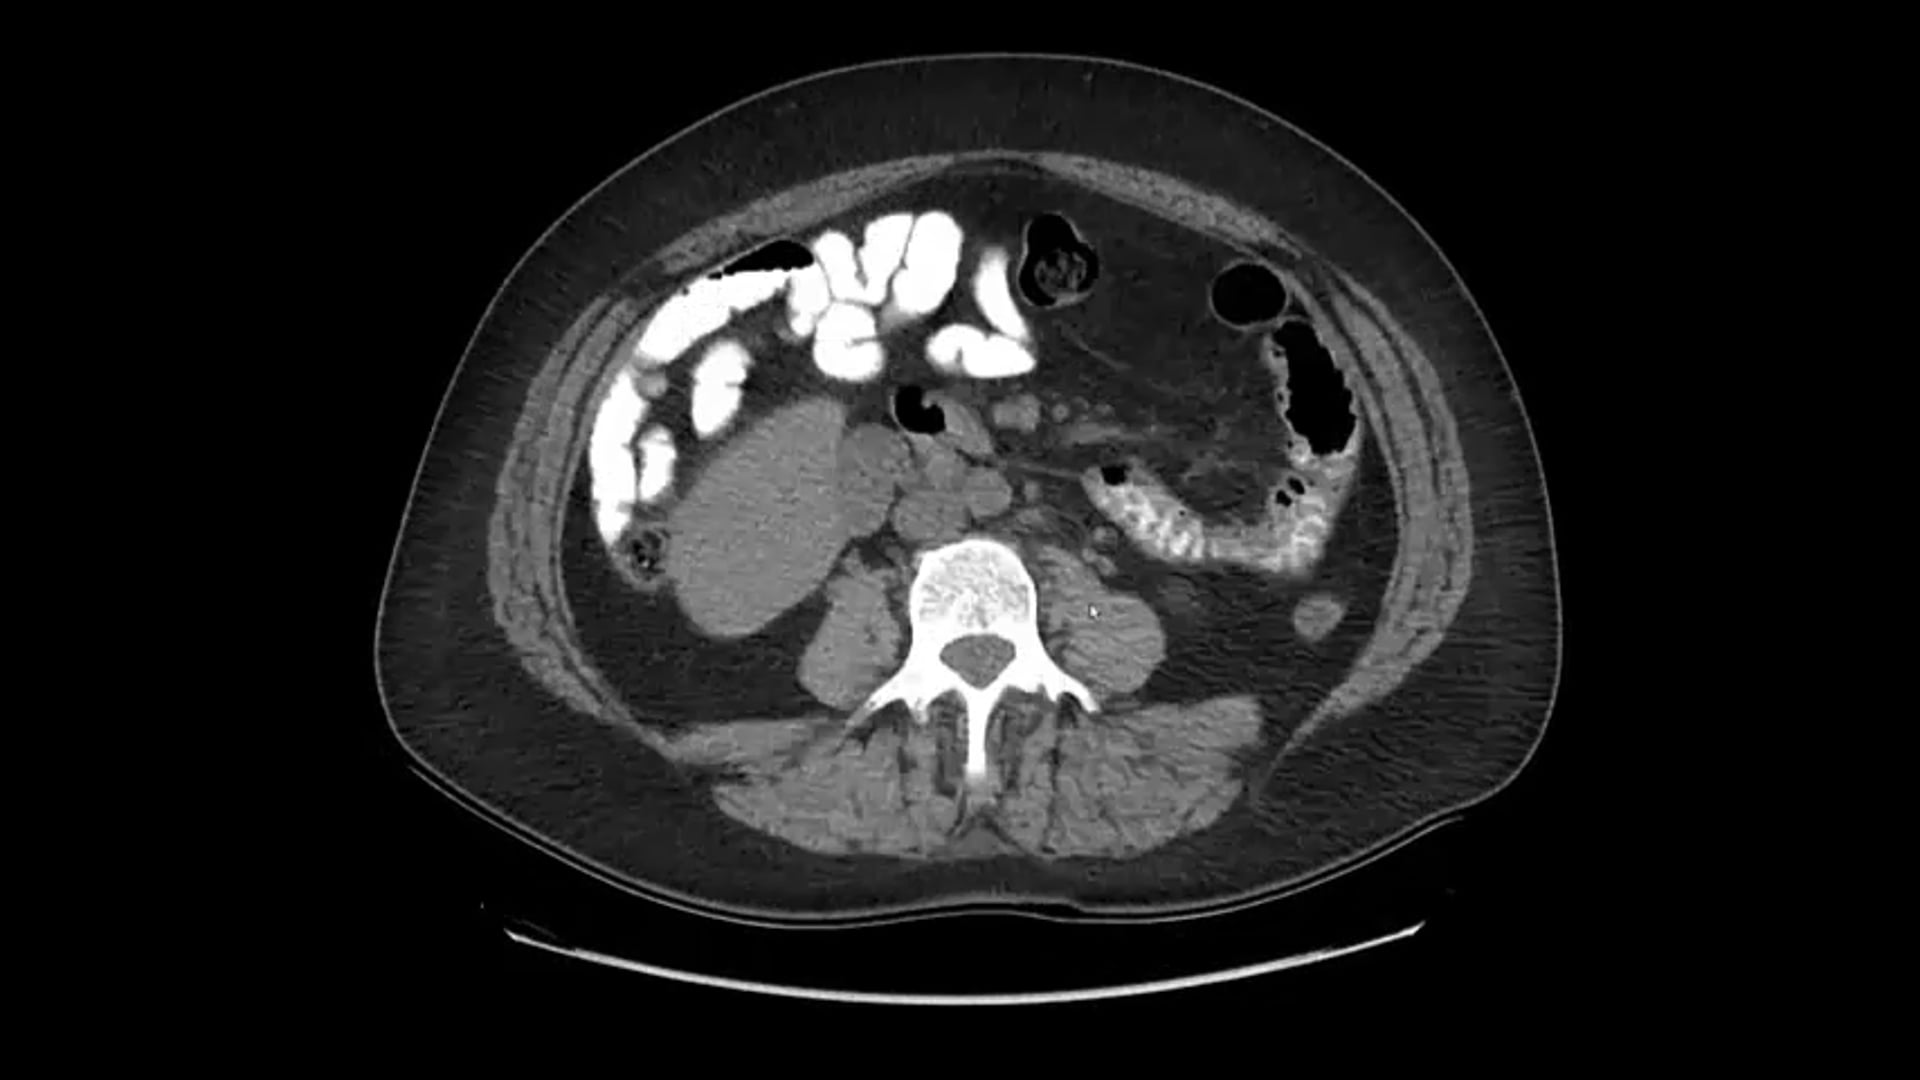

05/07/20 - Dr. Steven Frank - Radiation Oncology - GU Brachytherapy

MRI- Assisted Radiosurgery (MARS), LDR implants, prostate brachytherapy, MRI contouring